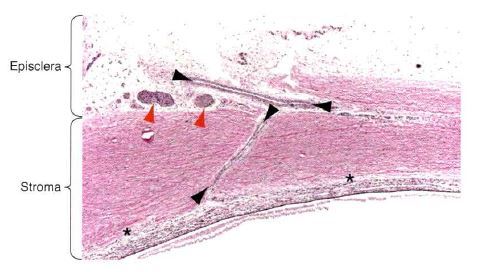

What is demonstrated below?

A

The normal sclera, the lamina fusca, ciliary arteries, and nerves.